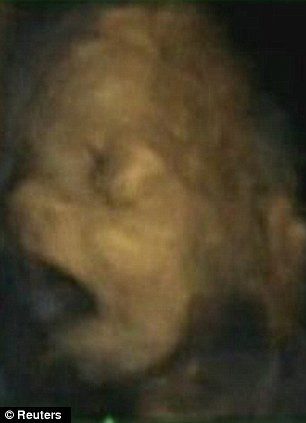

Anne karnındaki bebeğin esneme anları - Resim: 3

Reissland ve ekibinin gözlemi, gebeliğin 24 ve 36. haftaları arasındaki 8 kız ve 7 erkek bebekte yapıldı. Esnemenin 28. haftadan itibaren azaldığı, erkek ve kız bebeklerde önemli bir farklılığın olmadığı ortaya çıktı.